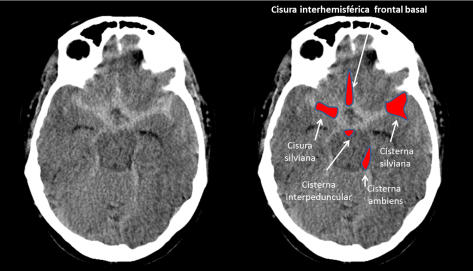

Continue reading →: Infarto cerebral talámico